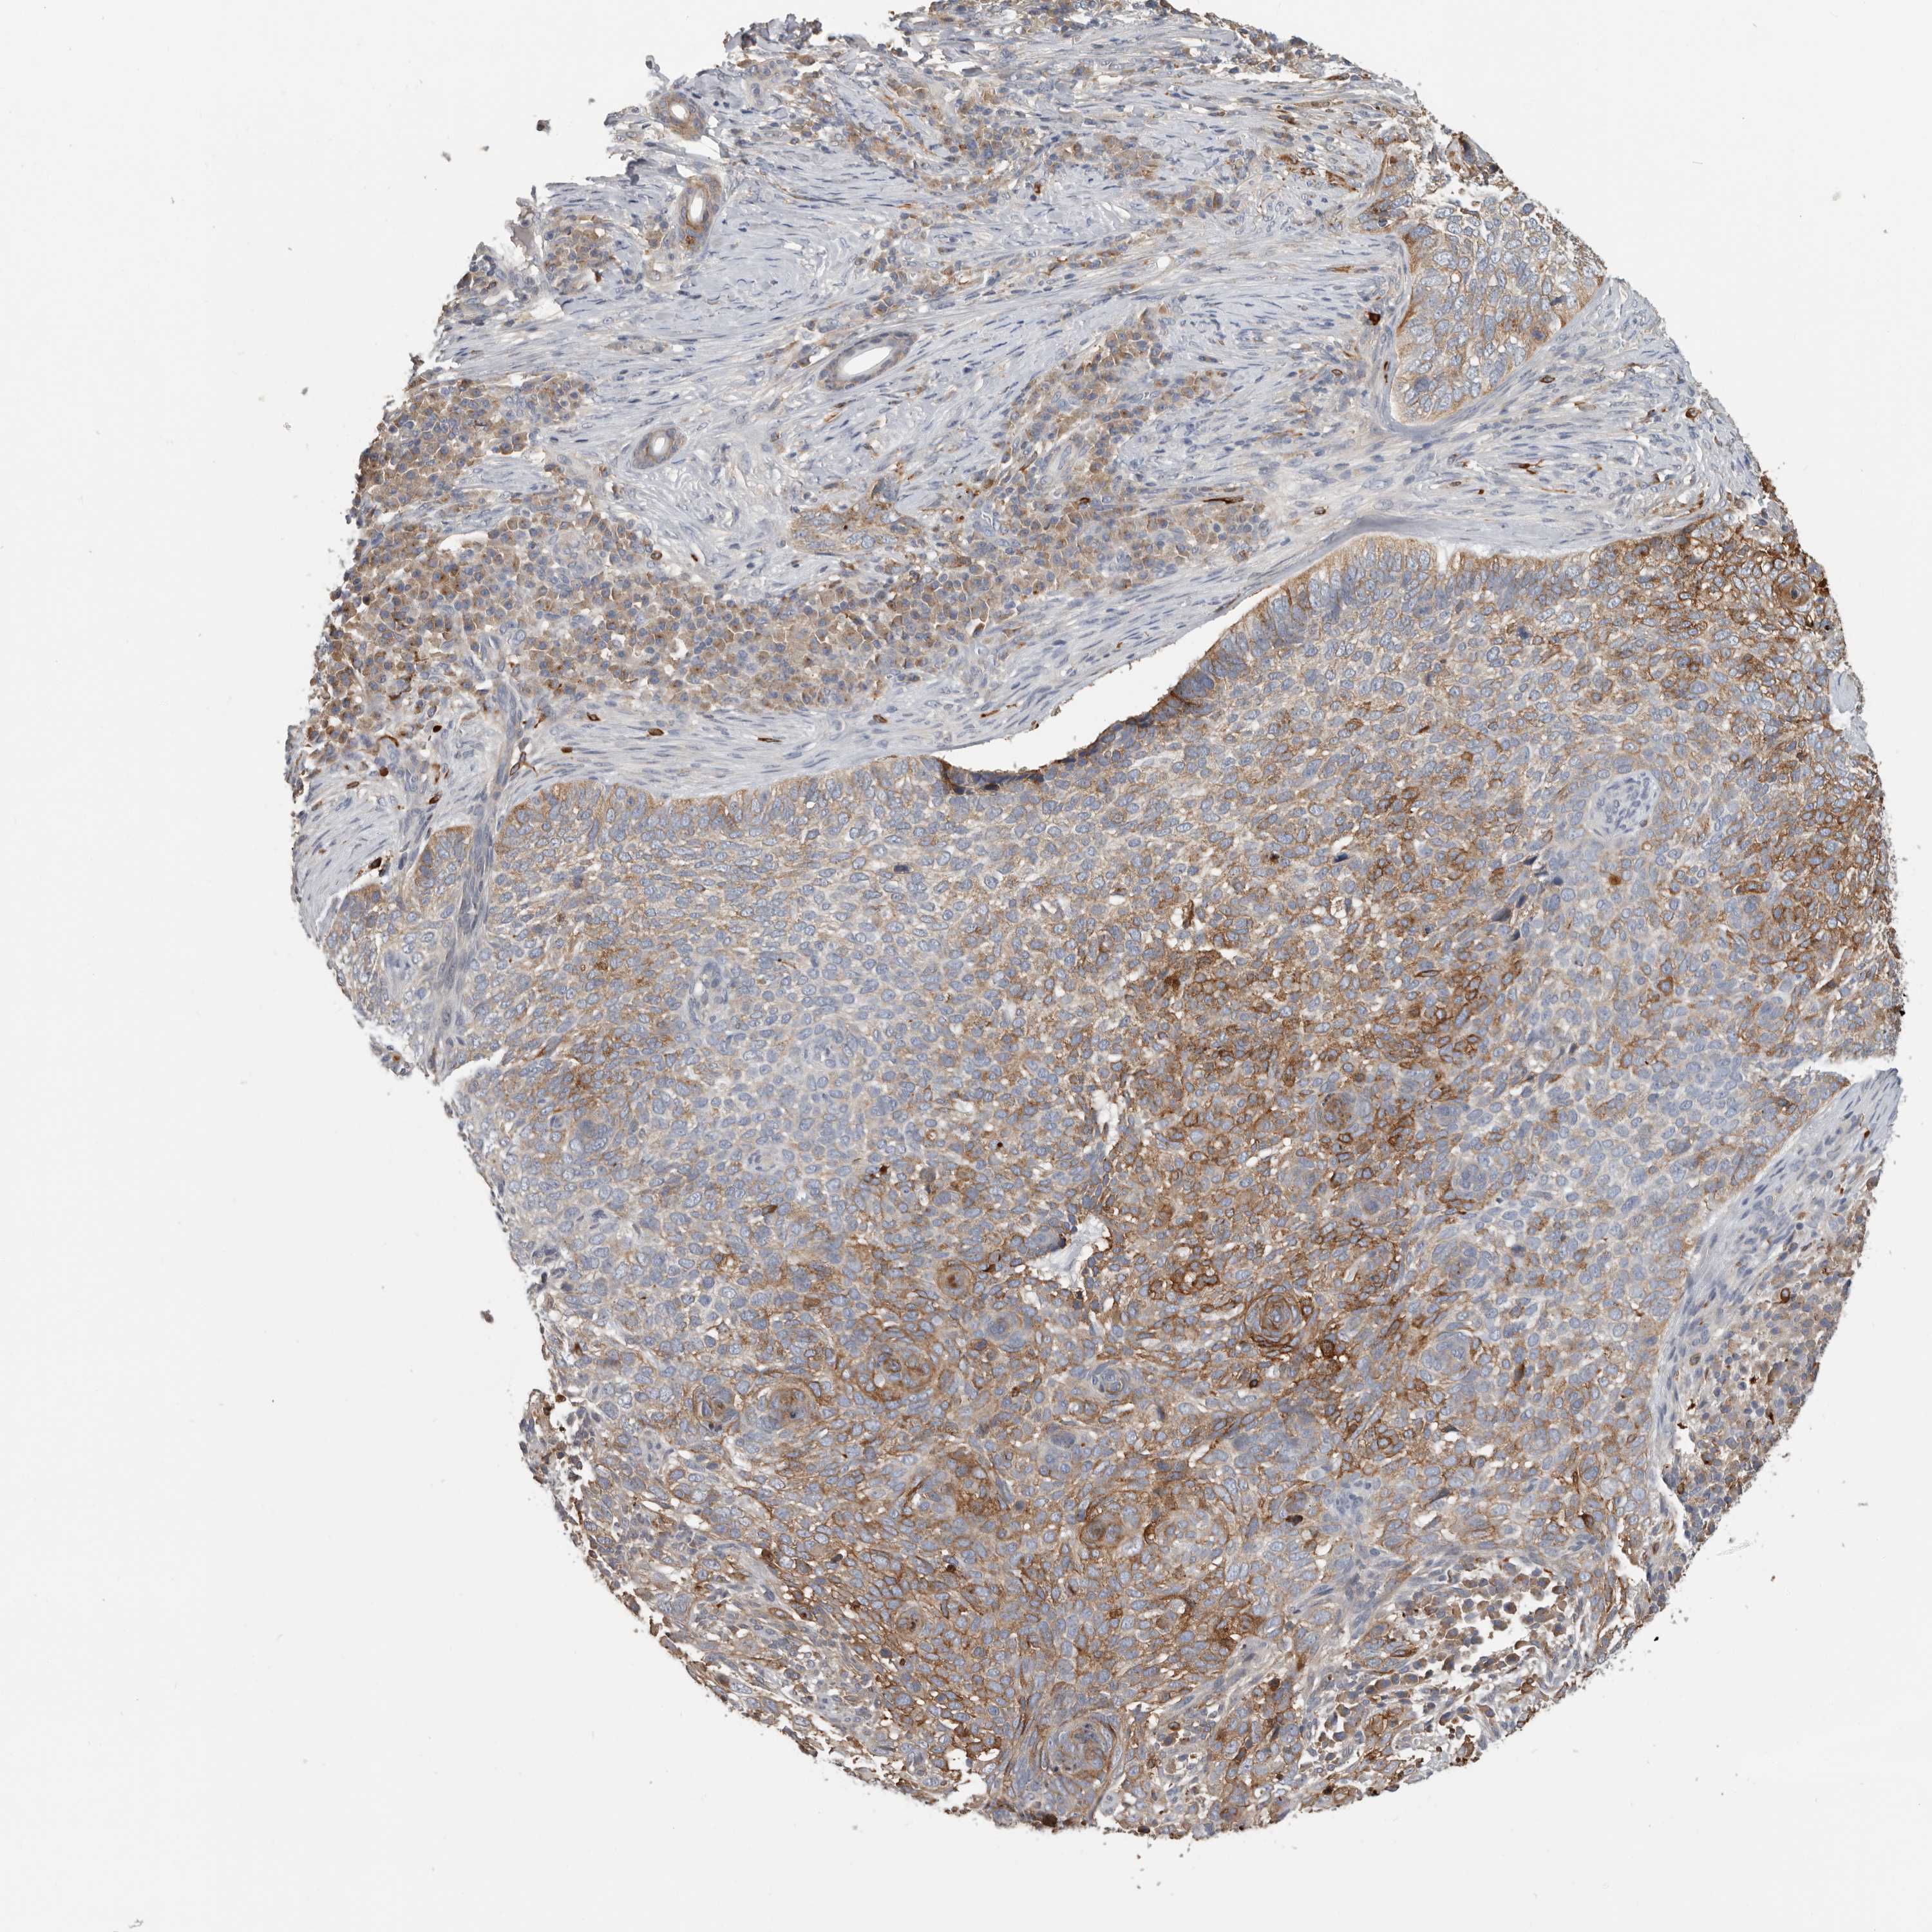

SKIN CANCER - Protein expressioni

A mouse-over function shows sample information and annotation data. Click on an image to view it in a full screen mode. Samples can be filtered based on level of antibody staining by selecting one or several of the following categories: high, medium, low and not detected. The assay and annotation is described here.

Antibody stainingi

Antibody staining in the annotated cell types in the current human tissue is reported as not detected, low, medium, or high, based on conventional immunohistochemistry profiling in selected tissues. This score is based on the combination of the staining intensity and fraction of stained cells.

Each image is clickable and will lead to virtual microscopy that enables deeper exploration of all samples and also displays staining intensity scores, fraction scores and subcellular localization as well as patient and tissue information for each sample.

Antibody CAB000153

Squamous cell carcinoma, NOS